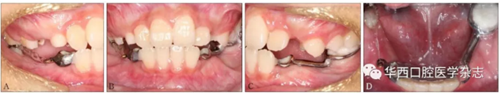

經過綜合分析及考慮患者的意愿,制定開窗-正畸協(xié)同治療方案,術前拔除尚未萌出的45牙為牽引46牙提供間隙,通過鑄造板將36、73、32、31、42、41、83牙連接成一整體,為牽引46牙提供支抗(圖4)。

A:右側像;B:正面像;C:左側像;D:下頜面像。

圖 4 矯治器初裝口內像

46牙開窗并將舌側扣粘接于近中面。用玻璃離子將鑄造板粘接在下頜,橡皮鏈通過83牙遠中的牽引鉤和46牙上的舌側扣相連,橡皮鏈牽引時對46牙產生一個順時針旋轉的作用力。術中牽引1個月時,見46牙產生順時針旋轉(圖5、6)。治療5個月時,46牙產生明顯的順時針旋轉,基本直立(圖7),由于此時下頜雙側乳尖牙脫落,下頜鑄造板無法固位,于是拆除矯治器,觀察隨診,待后期其余牙齒萌出后行全口固定正畸矯治。